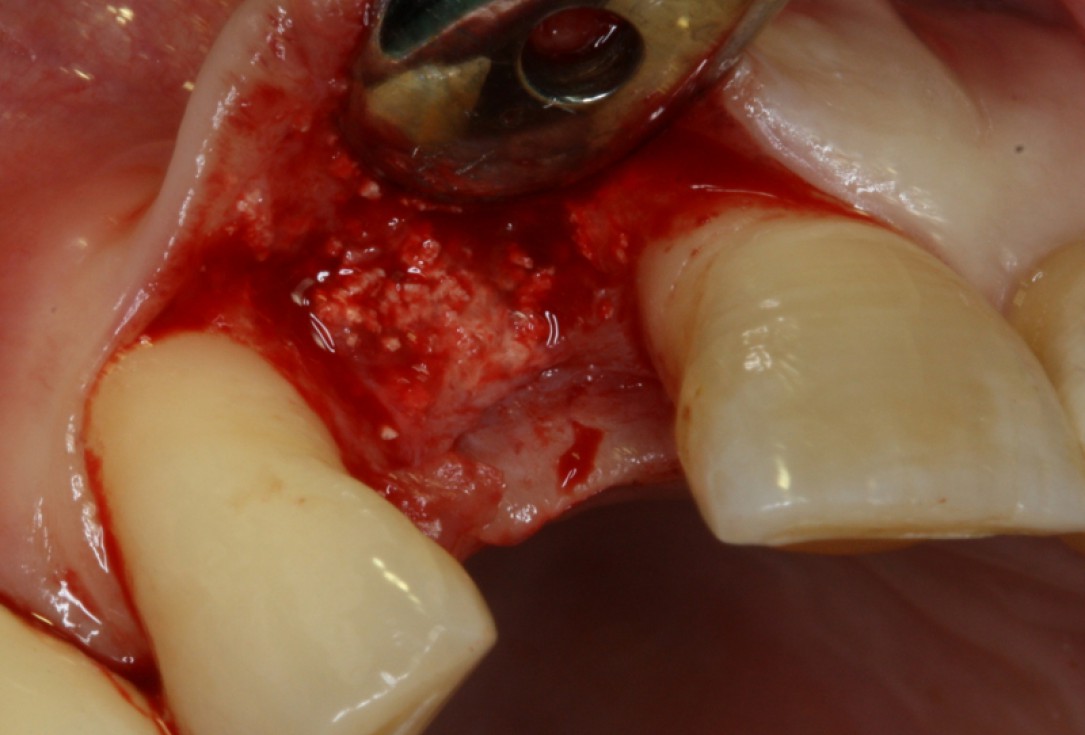

08/20 - Surgical presentation of the alveolar ridgeGBR with maxresorb® & Jason® membrane - Prof. Dr. Dr. D. Rothamel

09/20 - maxresorb® inserted into the extraction socketGBR with maxresorb® & Jason® membrane - Prof. Dr. Dr. D. Rothamel